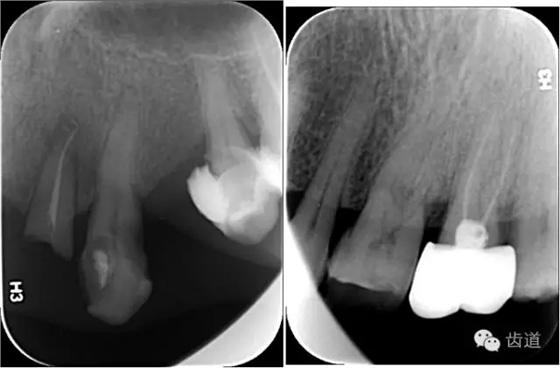

4、根分叉病變

根分叉病變

工具:彎探針(Nabers探針),頂端為鈍頭,有刻度,(可用彎尖探針代替)

方法:下頜磨牙,頰舌側(cè)中央探查;上頜磨牙,頰側(cè)中央及腭側(cè)近遠中探查

內(nèi)容:

分度:Glickman分度標(biāo)準(zhǔn)

Furcation

Furcation involvement

X線:根尖片、曲面斷層片(牙槽嵴頂,水平垂直吸收,程度)